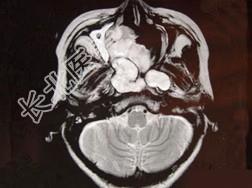

- 单项选择题女性,41岁, 鼻腔流脓涕3年,鼻部面部肿胀1年, 近来加重,MRI检查如图, 请选择最可能诊断 ( )

A、鼻腔内囊肿

B、鼻腔内出血

C、鼻腔软骨瘤

D、鼻咽癌

E、鼻腔血管瘤